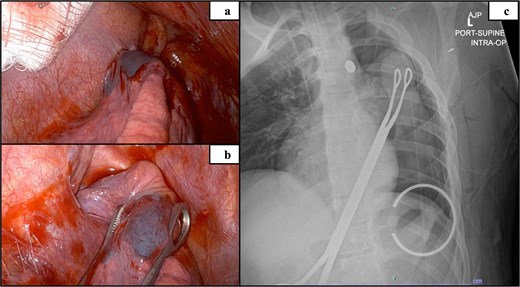

Intraoperative mediastinum adhesion visualized via robot (a), isolated upper lobe suspicious of containing bullet remnant (b) and intraoperative radiograph confirming bullet localized in the mediastinum (c).

All ports were placed and insufflation was restarted. The robot was docked and instruments were placed. The left arm (Port #1) used a tip-up grasper and the right arm (Port #3) used a long bipolar dissector. The 5 mm mediastinal defect was inspected; the phrenic nerve was directly posterior to the injury. The mediastinal pleura was opened longitudinally above and below the defect (Fig. 4a). A small amount of turbid fluid was evacuated, and the metal foreign body was identified (Fig. 4a and b). With gentle manipulation, the foreign body was rotated, indicating it was not lodged in a structure (Fig. 4c). There was no bleeding to indicate vascular injury. The foreign body (Fig. 4d and e) was grasped and removed in its entirety without damage to surrounding structures. The mediastinal defect was hemostatic and no further dissection was performed. A posterior intercostal nerve block was performed on the intercostal spaces 4–11, and cryoablation of the intercostal nerves level 5–11. The instruments, camera, and sponge were removed, and the robot was undocked. A 24Fr chest tube was placed, the lung was inflated, the chest was closed, and the patient was extubated. The estimated blood loss was 10 ml. The operative time was 1 hour 38 minutes. The foreign body (Fig. 5) was sent to the appropriate authorities.